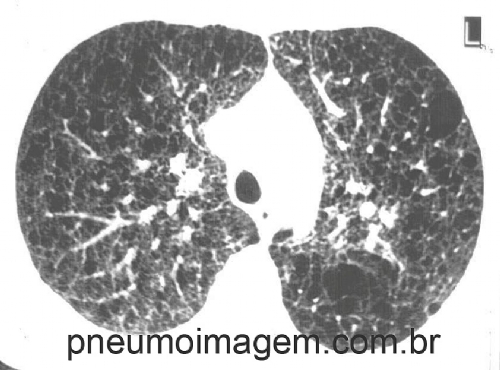

A LAM é uma doença rara e progressiva que basicamente afeta mulheres jovens no período fértil de sua vida. A doença é caracterizada pela hiperproliferação anormal de células de músculo liso nos pulmões, associada com a formação de cistos parenquimatosos difusos e dispneia.